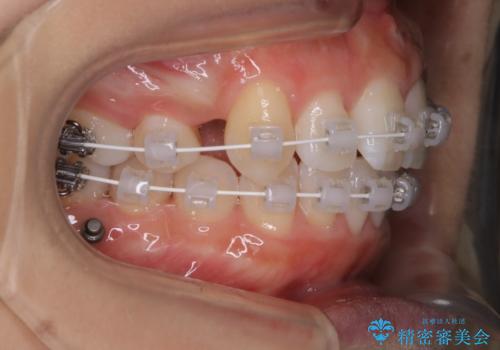

ワイヤー矯正 抜歯本数を最小限にし、八重歯のない歯並びに

- 上顎の八重歯が気になるとのことで来院されました。

左側のかみ合わせは、歯1本分かみ合わせが前にずれていました。上顎左右の奥歯を2本抜歯しています。

下顎は、歯の側面を少し削ることで歯並びを整えました。

上顎と下顎の奥歯の抜歯(計4本)を行う治療方法もありますが、口元のバランスのことも考え、上顎の抜歯のみで、治療を行いました。

八重歯でがたつきは重度でしたが、きれいな歯並びにすることができました。

がたつきだけでなく、奥歯の噛み合わせのずれの調整もしっかり行いました。